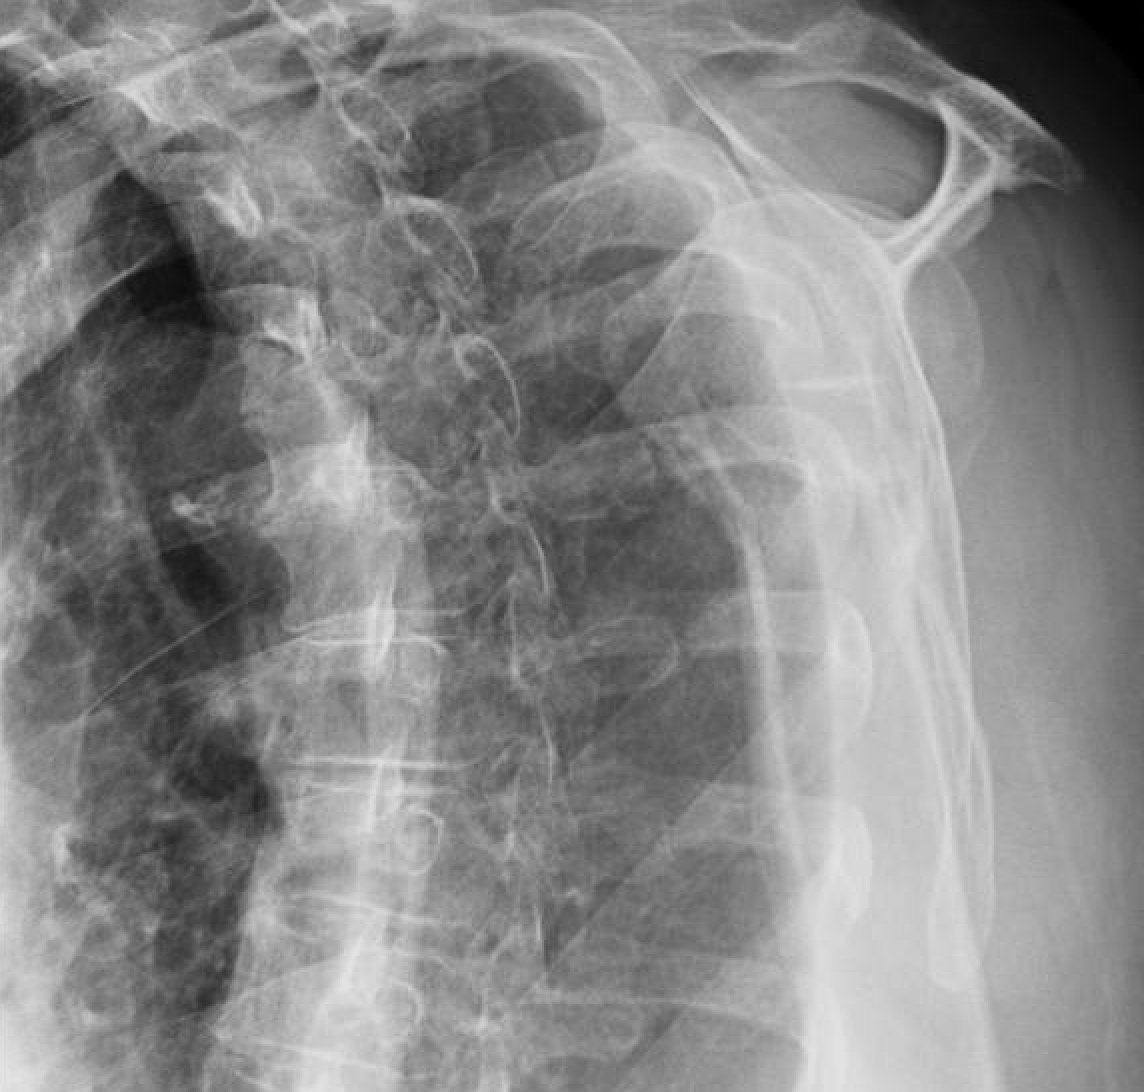

Shoulder and Elbow Surgery Non operative treatment of the fracture of Elbow Fracture Non Operative Protocol Rom by end of 2nd week should be at least 15 to 115. This protocol is recommended for mason’s type i fracture or type ii or iii with orif. • protocol must be altered based on fixation strength at. Passive and active elbow rom as tolerated: The following guidelines for stable elbow fractures and simple dislocations. • continue to control. Elbow Fracture Non Operative Protocol.

From shoulderelbow.blogspot.com

Shoulder and Elbow Surgery Non operative treatment of the fracture of Elbow Fracture Non Operative Protocol This protocol is recommended for mason’s type i fracture or type ii or iii with orif. The following guidelines for stable elbow fractures and simple dislocations. • continue to control pain and edema as needed •. • protocol must be altered based on fixation strength at. Passive and active elbow rom as tolerated: Rehabilitation protocol nonoperative radial head fracture. Rom. Elbow Fracture Non Operative Protocol.

Shoulder and Elbow Surgery Non operative treatment of the fracture of Elbow Fracture Non Operative Protocol Passive and active elbow rom as tolerated: • protocol must be altered based on fixation strength at. The following guidelines for stable elbow fractures and simple dislocations. This protocol is recommended for mason’s type i fracture or type ii or iii with orif. Rehabilitation protocol nonoperative radial head fracture. • continue to control pain and edema as needed •. Rom. Elbow Fracture Non Operative Protocol.